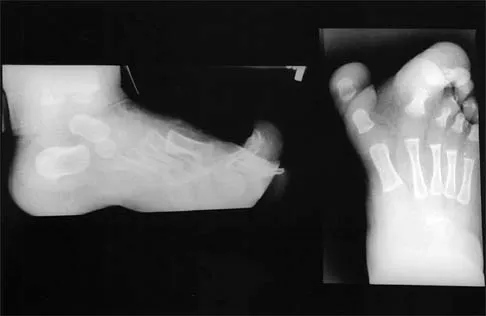

The inheritance of the deformity shown in Figure 1 is most commonly

A 15-year-old boy with a type I hereditary sensory motor neuropathy (Charcot-Marie-Tooth disease) reports recurrent ankle sprains and significant pain in the hindfoot and midfoot despite orthotic management. Examination reveals that he walks with a drop foot and has dynamic clawing of the toes. Clinical photographs of the left foot are shown in Figure 7. Management should consist of